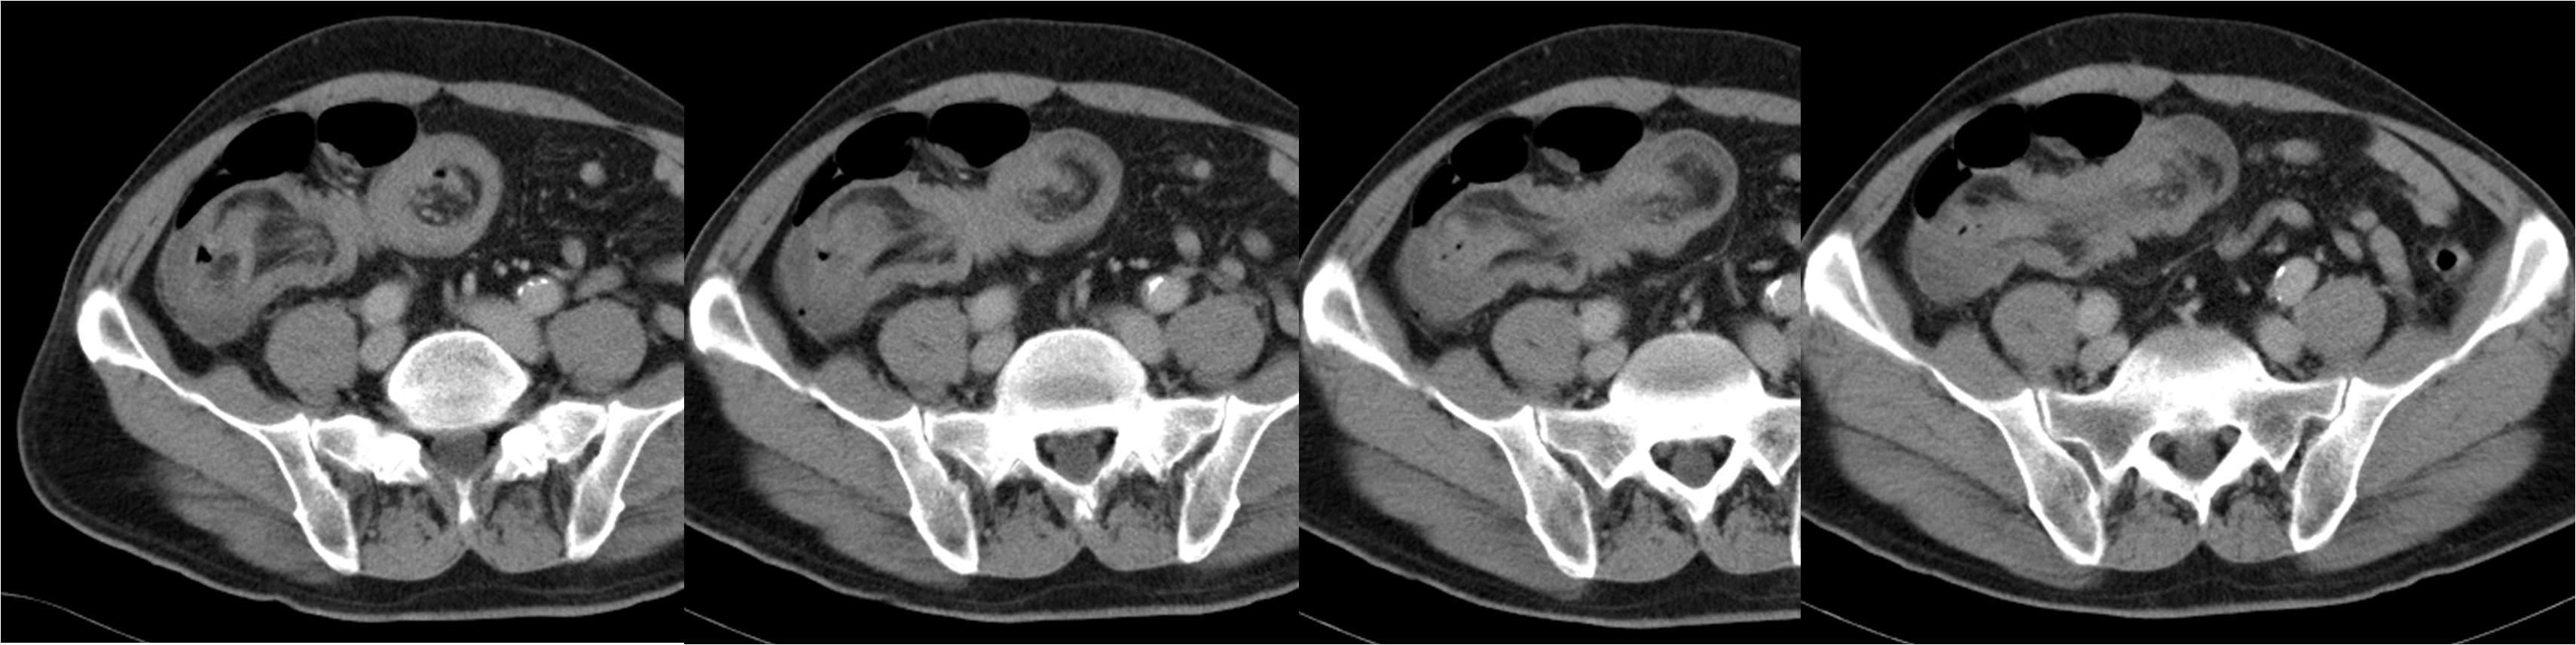

Se presenta el caso de un paciente de 68 años con invaginación intestinal secundaria a un lipoma submucoso de íleon. Se trata de una entidad rara en adultos y que suele ser debida a una lesión orgánica. La manifestación clínica se caracteriza por vómitos, dolor abdominal y melenas.

Se presenta el caso de un paciente al que tras la realización de una colonoscopia y un TAC abdominal, se realizó una resección ampliada de ciego e íleon terminal.

En la actualidad la precisión del diagnóstico etiológico de las invaginaciones ha aumentado gracias al desarrollo de las pruebas de imagen, como el TAC. Se recomienda un tratamiento quirúrgico precoz, sin desinvaginación intraoperatoria dado el elevado riesgo de presentar una lesión maligna o isquémica en el adulto.